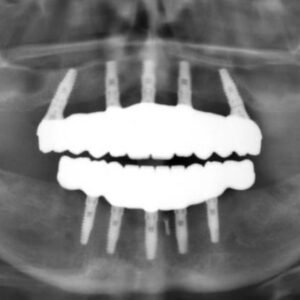

Our experienced faculty, comprised of specialists in implant dentistry, share their insights from years of practical experience, ensuring that you gain not just theoretical knowledge but also real-world applications. By the end of this course, we ensure that participants feel confident and ready to integrate implantology into their own practices.